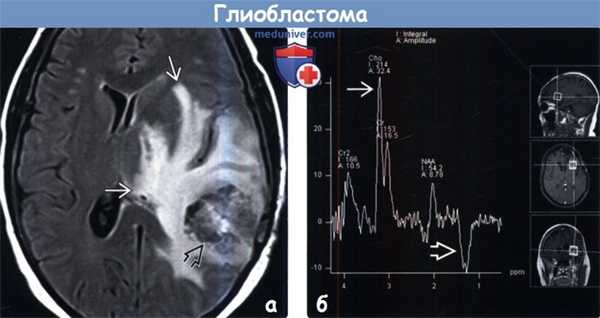

(а) МРТ, FLAIR, аксиальный срез: у пациента с МГБ определяется гетерогенное объемное образование и протяженная зона изменения сигнала вокруг него, что является признаком комбинации распространения клеток опухоли и вазогенного перифокального отека. С позиции патологии клетки опухоли обнаруживаются за пределами областей изменения сигнала.

(б) МР-спектроскопия: у пациента с рецидивирующей МГБ определяется классический МР-спектр, характерный для злокачественной опухоли, с выраженным подъемом пика холина (Cho), низким пиком NAA на 2,02 ppm и инвертированным пиком лактата на 1,33.1. Общие характеристики глиобластомы: